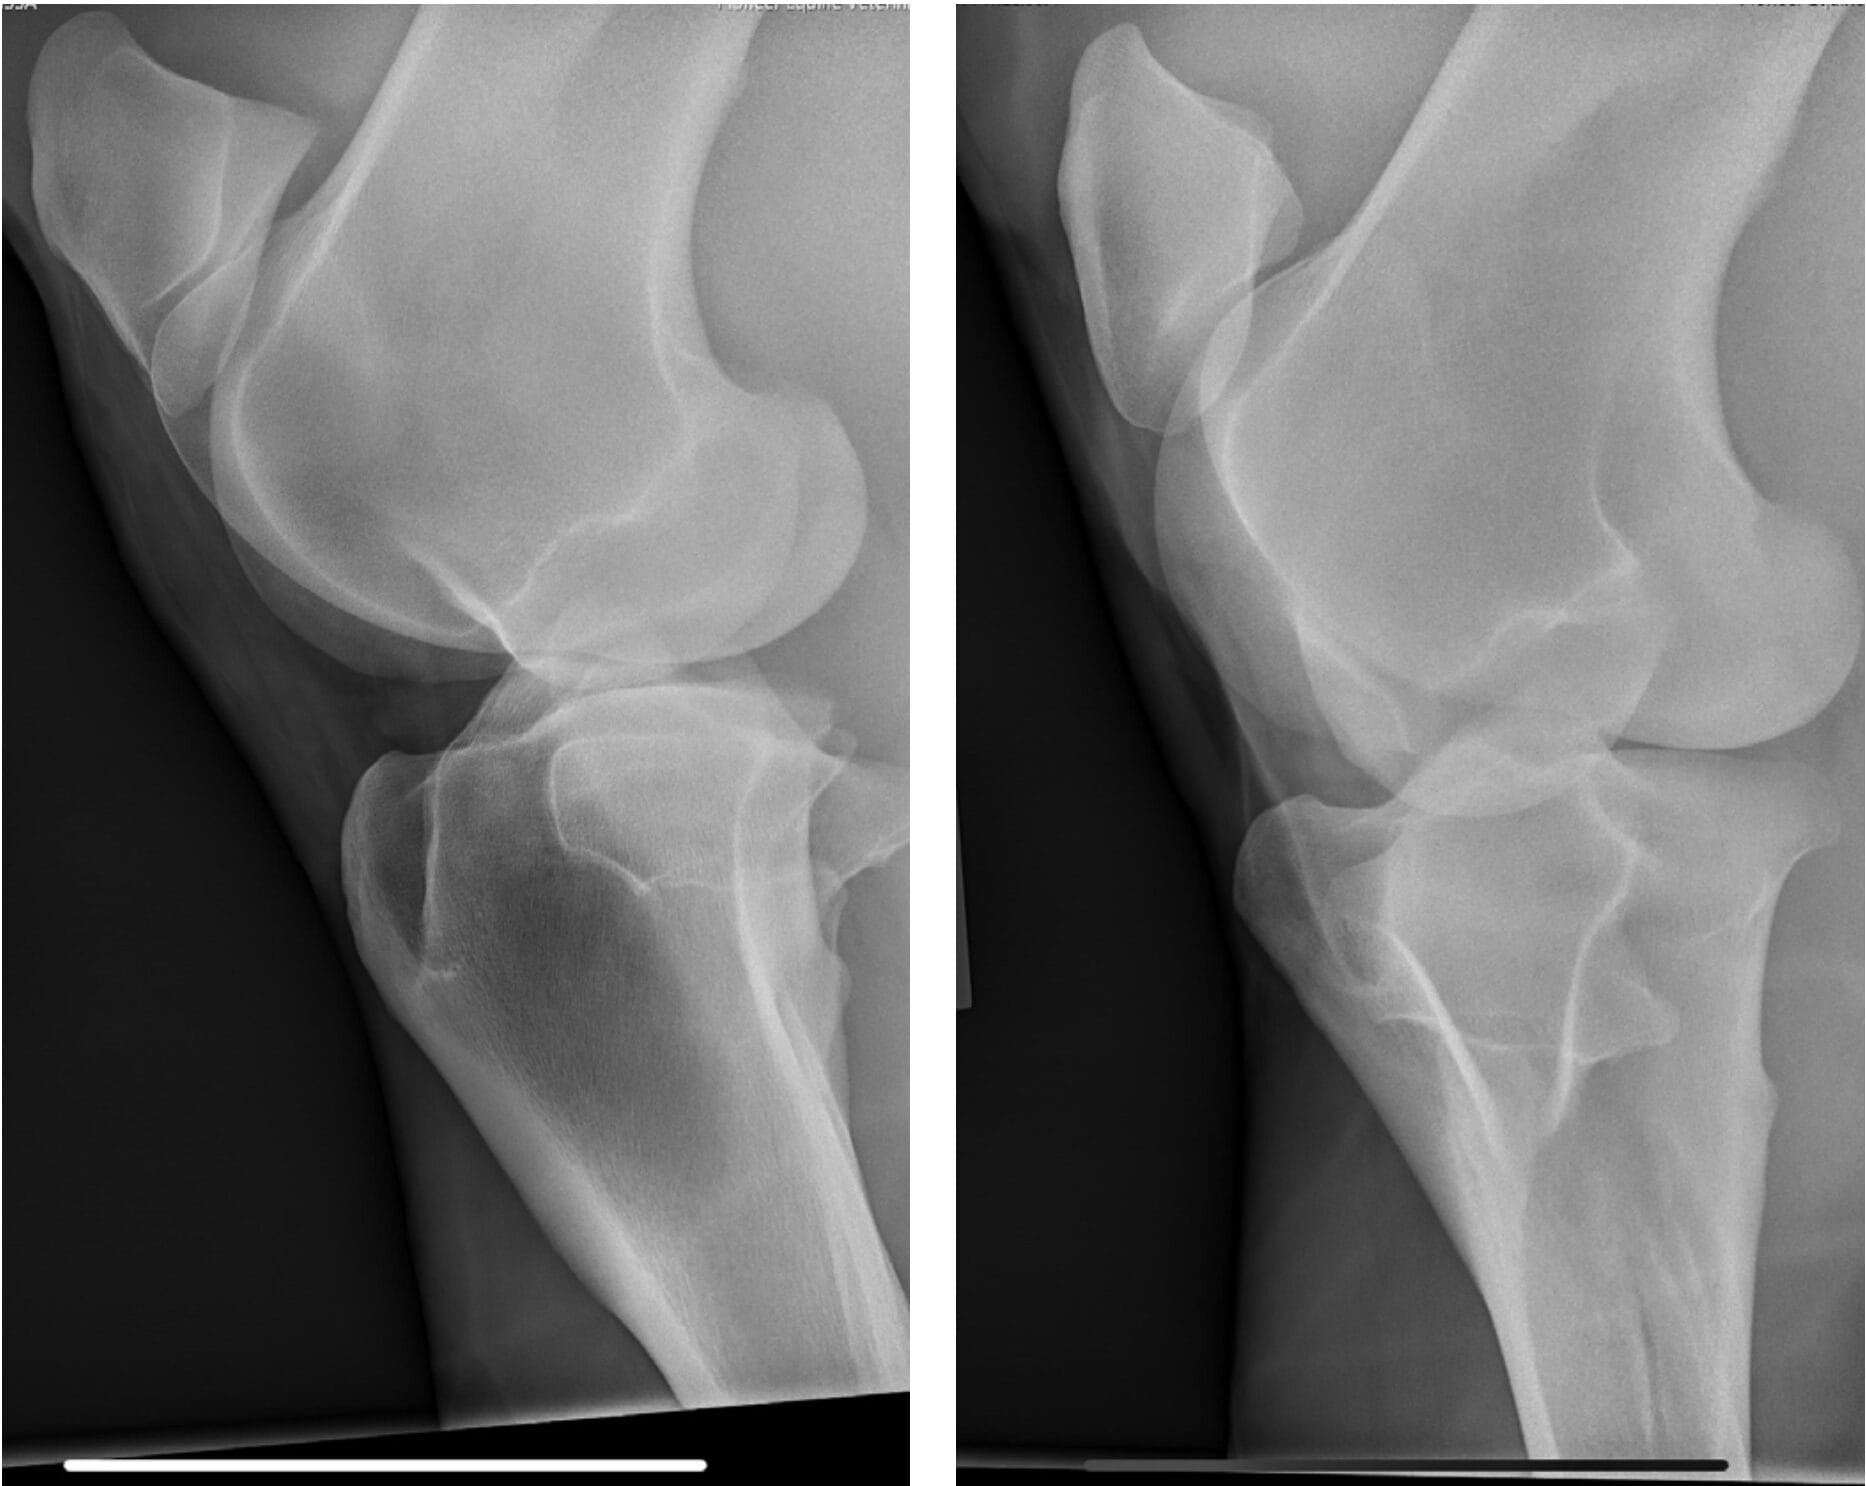

In April 2023, Bella developed a right hind lameness that was characterized by a toe drag, decreased push and mild abduction of the limb. The lameness was worse with the leg on the outside of the circle. She was negative to lower limb flexion and 1+ out of 5 positive to upper limb flexion. Lameness resolved with an intra-articular medial femorotibial block. Radiographs of the right stifle were unremarkable.

Ultrasound of the right stifle showed moderate medial femorotibial joint effusion with small hyperechoic particles, consistent with thin cartilage debris. There was a 1.5 cm x 0.5 cm defect in the abaxial portion of the medial trochlear ridge.

There was mild cranial meniscotibial ligament desmopathy. There was mild degenerative change in the axial portion of the medial meniscus. There was mild sonographic evidence of axial subchondral bone remodeling of the medial condyle at the level of the most weight-bearing portion. Ultrasound of the left stifle showed similar but less pronounced changes.